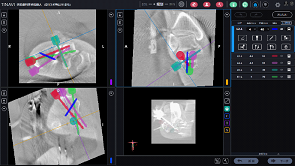

术中螺钉路径规划,机器人辅助置钉